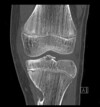

6 XR findings of degenerative arthritis?

1) Asymmetric joint space narrowing - worsened by WB views 2) Sclerosis of juxta-articular bone 3) Osteophytes 4) Bone spurs 5) Subchondral cysts 6) Minimal to no osteoporosis

126

List 3 XR findings of late Rheumatoid Arthritis

Symmetric joint space narrowing Osteoporosis of periarticular bone Marginal erosions